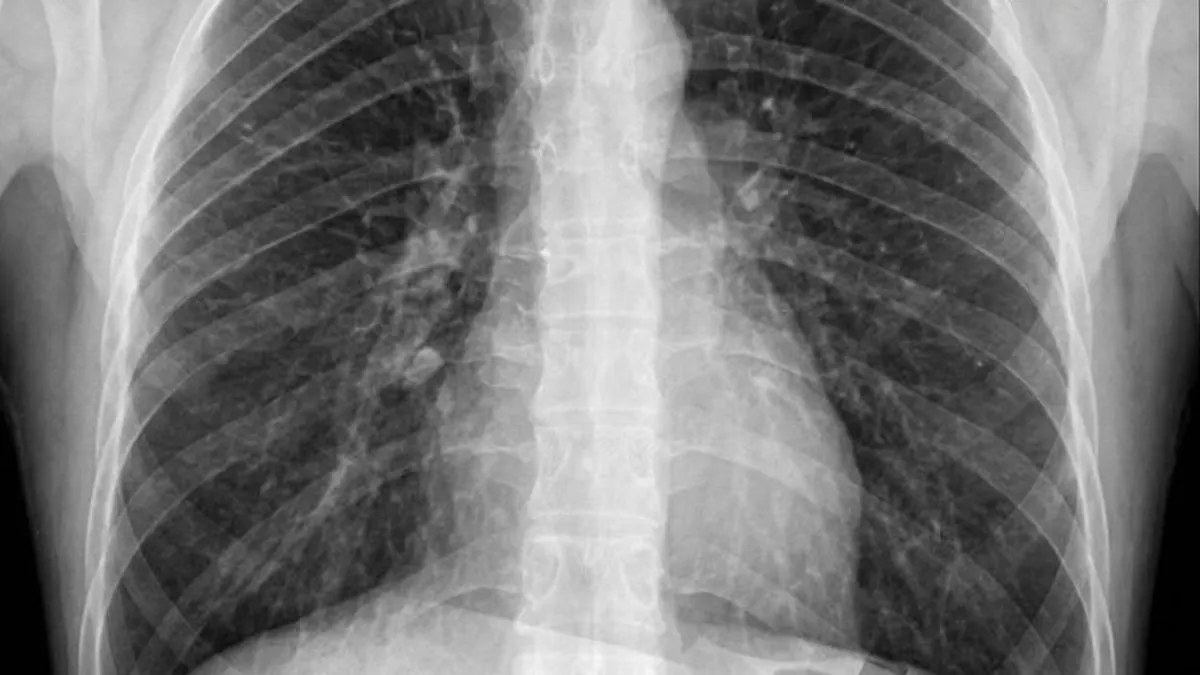

Rutinsko vađenje umnjaka za muškarca iz Brazila pretvorilo se u pravu dramu nakon što je počeo osjećati neobično i bolno štucanje. Rendgenska snimka prsnog koša otkrila je bizaran uzrok njegovih tegoba – jedan od izvađenih umnjaka završio mu je u plućima.

Artur iz São Paula svoju je priču podijelio na Redditu, gdje je objavio i rendgensku snimku. Ispričao je da su mu zubari rekli kako mora izvaditi sva četiri umnjaka, a kako se jako boji igala, tražio je da tokom zahvata bude pod sedacijom.

Snimka je potvrdila sumnju – umnjak mu je završio u plućima. Doktori su mu objasnili da pacijent u takvoj situaciji obično zakašlje ili proguta zub, no kako je Artur bio pod sedacijom, taj refleks nije radio.

Zub su mu potom izvadili bronhoskopijom, postupkom u kojem liječnici malom kamerom ulaze u dišne putove i pluća kako bi pronašli i uklonili strano tijelo.